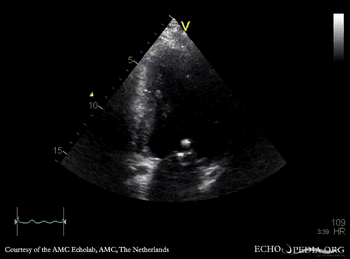

| PLAX: vegetations on PMVL | A4CH |